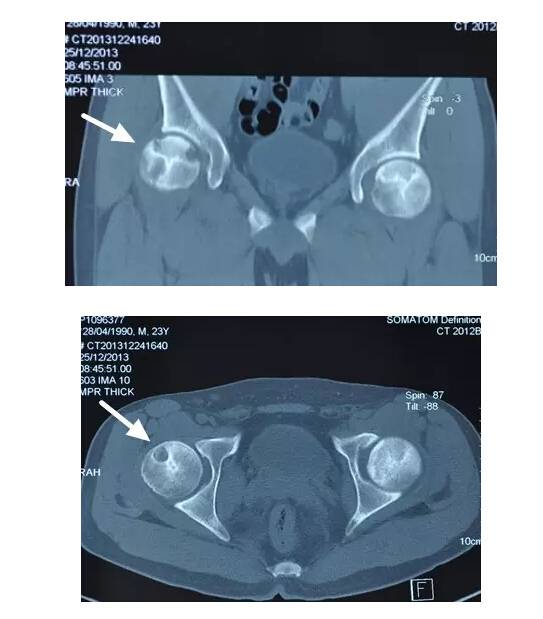

II期病人有髋部症状,磁共振出现异常,X线片显示股骨头出现透光和硬化改变

III期磁共振出现异常,X线片显示软骨下塌陷(新月征),股骨头内出现空洞,股骨头没有变扁

II期和III期的患者治疗方法相同,因为此时股骨头虽然还没有变形,暂时还不需要行人工关节置换术,但是股骨头已经出现空洞,随时股骨头就会塌陷变形,所以单纯的股骨头减压术是不能达到治疗效果的。这时就需要在股骨头减压的同时,植入一根支撑棒,顶住股骨头空洞区,防止股骨头在负重的情况下过早塌陷。其他治疗同之前相同,口服以上药物,定期复查,密切观察病情发展,尽量避免重体力劳动和爬山爬楼。